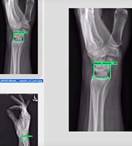

Wrist Bone

Wrist Bone Trauma AI

Machine Learning-Aided Diagnosis Enhances Human Detection of Perilunate Dislocations.

Luan A, von Rabenau L, Serebrakian AT, Crowe CS, Do BH, Eberlin KR, Chang J, Pridgen BC. Machine Learning-Aided Diagnosis Enhances Human Detection of Perilunate Dislocations. Hand (N Y). 2025 Jan 15:15589447241308603. doi: 10.1177/15589447241308603. Epub ahead of print. PMID: 39815415; PMCID: PMC11736725.

Pridgen B, von Rabenau L, Luan A, Gu AJ, Wang DS, Langlotz C, Chang J, Do B. Automatic Detection of Perilunate and Lunate Dislocations on Wrist Radiographs Using Deep Learning. Plast Reconstr Surg. 2024 Jun 1;153(6):1138e-1141e. doi: 10.1097/PRS.0000000000010928. Epub 2023 Jul 17. PMID: 37467052.